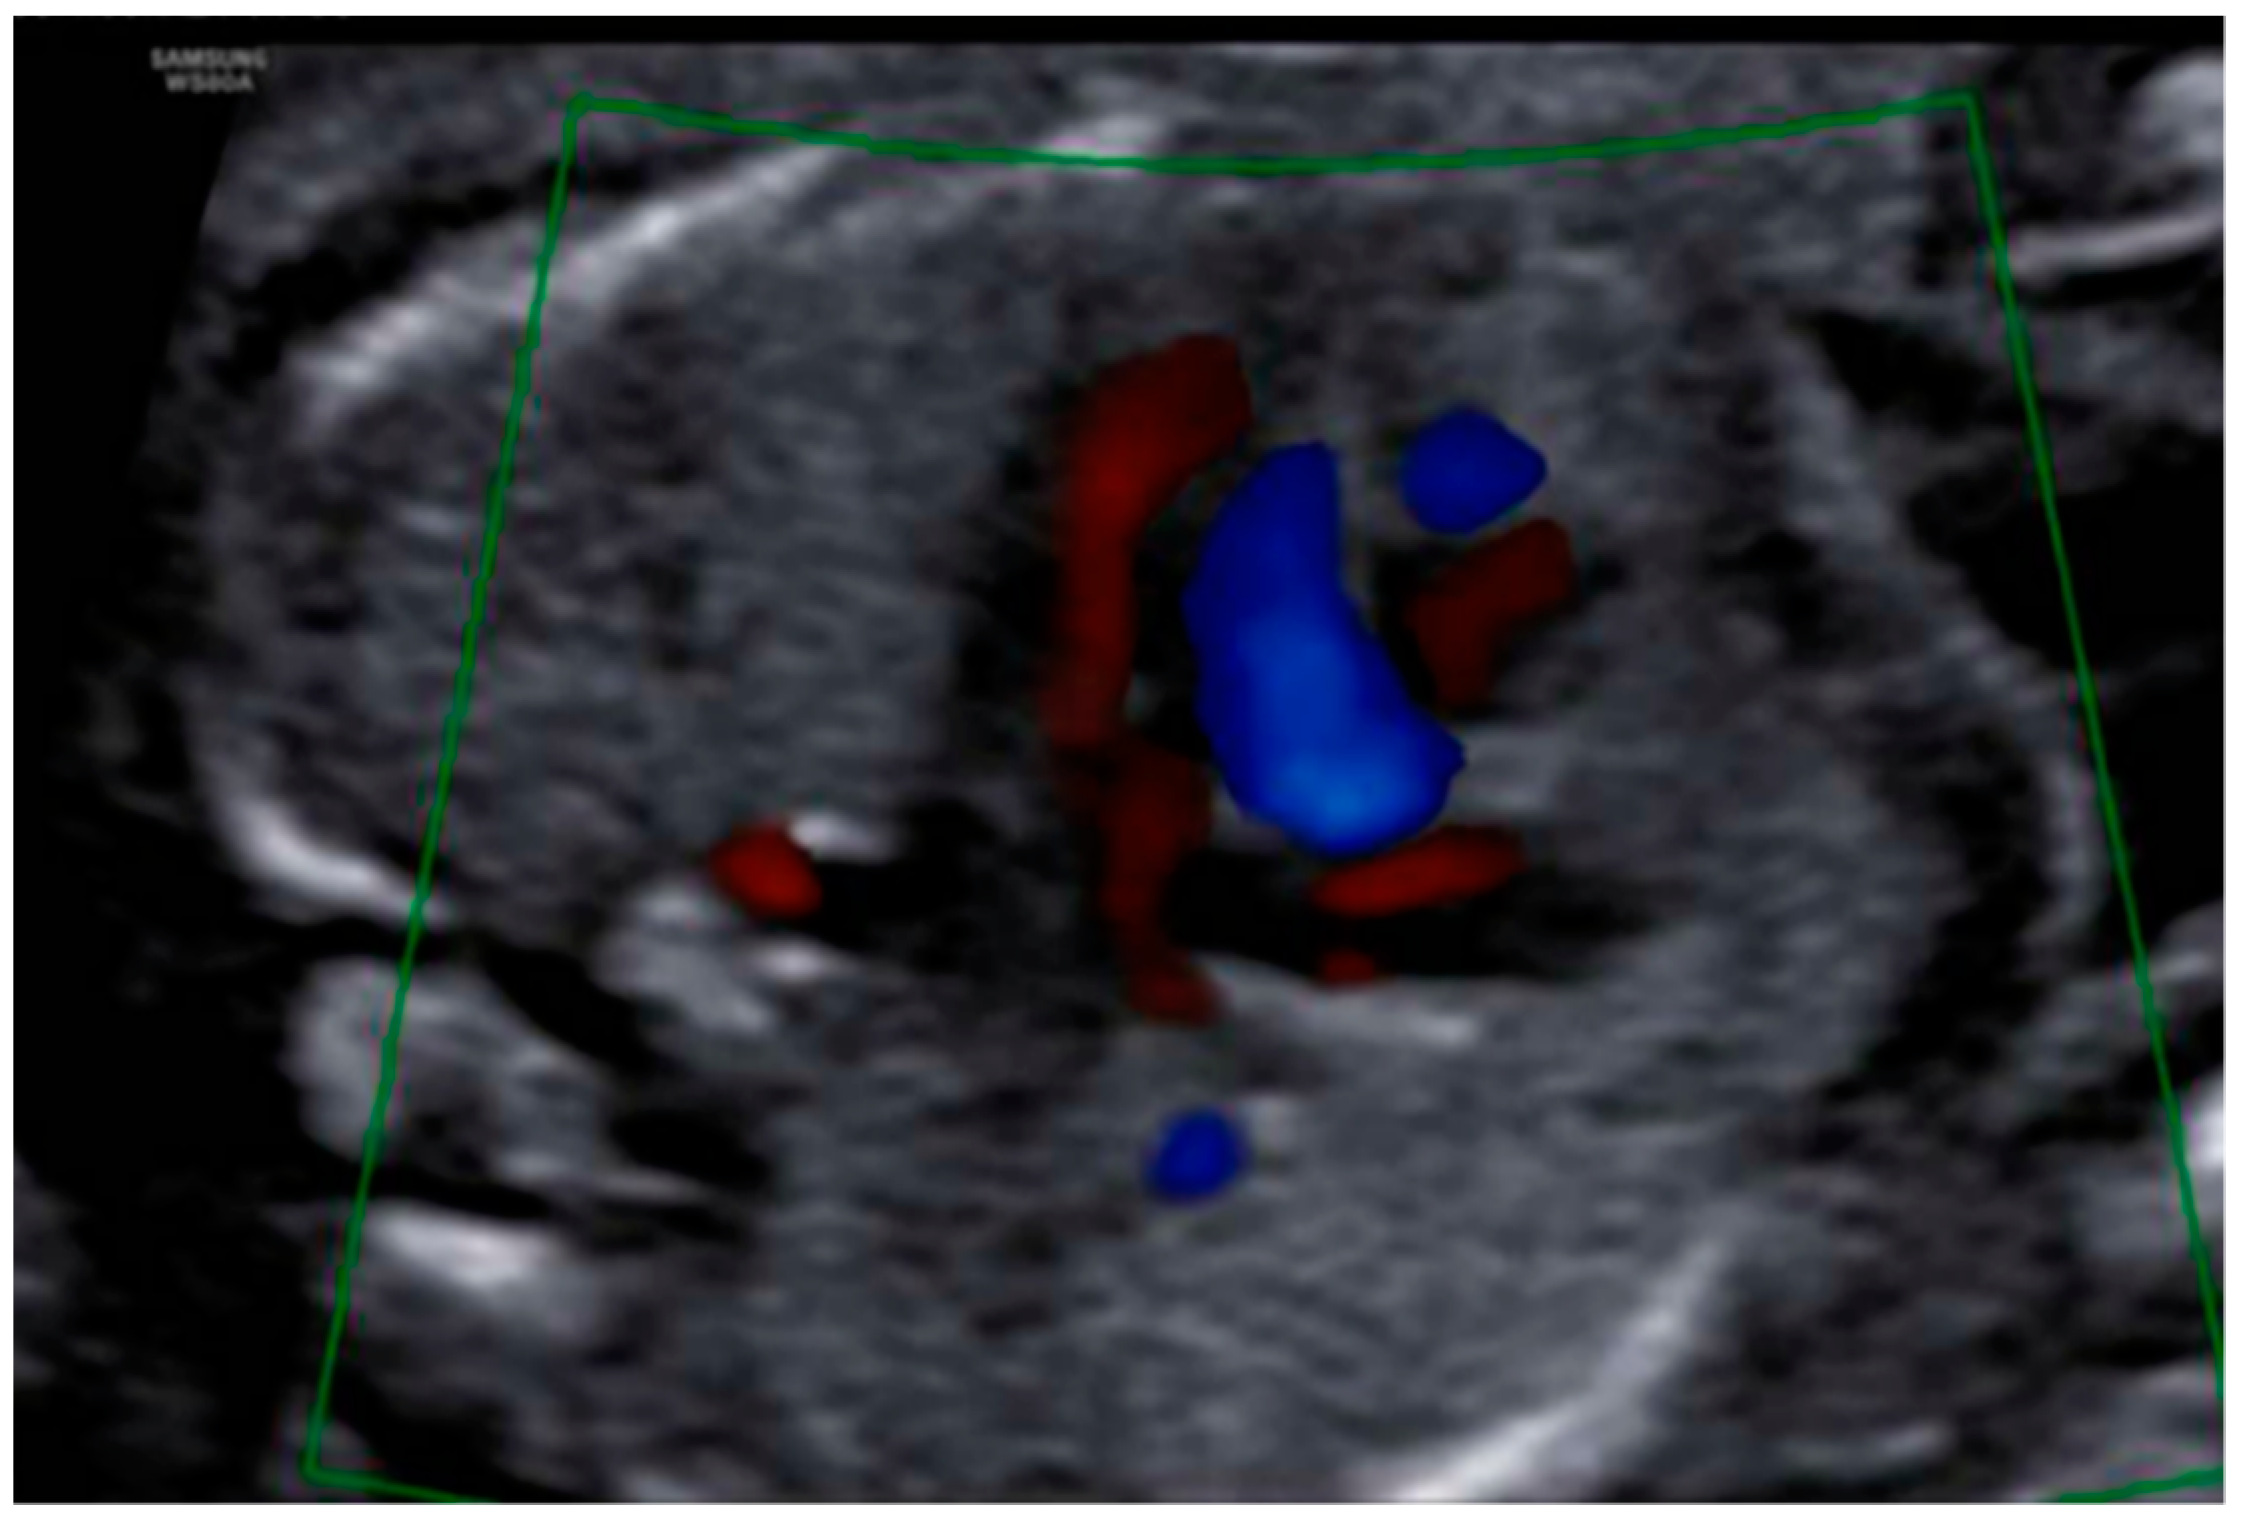

3. Results: Case Presentation